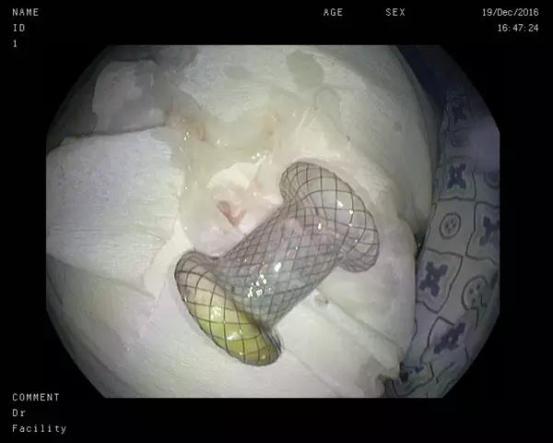

囊液充分引流后支架被完好取出

此次患者郑某、耿某均于半年前发生胰腺炎,病情稳定后逐渐出现腹胀、进食后呕吐等梗阻症状,入院后经CT检查发现巨大胰腺假性囊肿形成。我院东院消化内科以张春清主任、张俊勇副主任医师为首的超声内镜介入团队,带领冯华主治医师、王广川主治医师,结合疾病特点和既往经验,反复研究琢磨,借鉴先心病室间隔缺损“封堵器”的原理,创新采用特制双蘑菇头覆膜支架代替传统胆道支架,通过膨大的双蘑菇头将胃壁和囊壁牢牢卡在一起,从而避免支架滑脱的可能,另外宽大的蘑菇头使术者可以轻松的操作鼻胃镜经支架中间孔道进入囊腔,进而对囊内坏死物质进行冲洗和清理,促进患者恢复。两位患者在植入双蘑菇头支架后,腹胀症状迅速缓解,即可正常饮食,经4周引流,复查CT囊肿基本消失,支架无任何移位,遂在内镜下将支架取出,胃壁创口愈合良好。